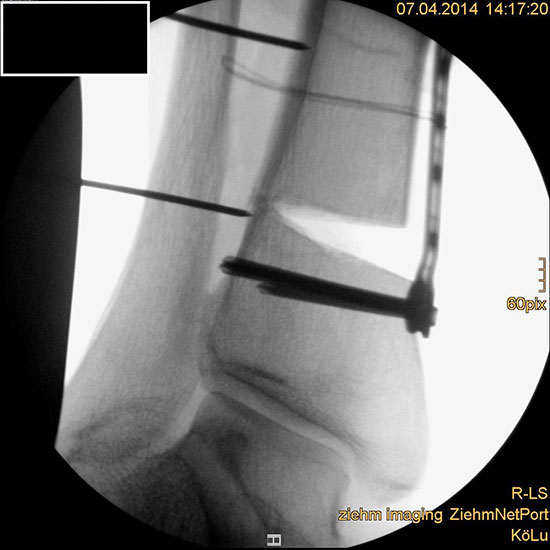

Auch hier wird die Korrektur im CORA (Center oft Rotation and Angulation) durchgeführt. Primär werden intraoperativ unter Bildwandler Kontrolle Kirschner Drähte als Sägelehre konvergierend eingebracht. Dann wird der geplante medialbasige Keil mit der oszillierenden Säge entfernt. Die laterale Kortikalis sollte geschont werden, sie dient als Drehpunkt für die Osteotomie. Die Osteosynthese kann dann im Sinne einer Zuggurtung ein besonders stabiles Konstrukt bilden. Liegen mehrdimensionale Deformitäten vor, die eine Korrektur in Translations- und Rotationsebene erfordern, ist eine Durchtrennung der lateralen Kortikalis notwendig, ebenso bei ausgedehnten Korrekturen mit Keilhöhen über 10mm 218.

Wir benutzen zur Osteosynthese 3,5 mm LCP T-Platten. In der intraoperativen Röntgenkontrolle kann im seitlichen Bild die Zentrierung des Talus überprüft werden, und ggf. durch eine milde extendierende oder flektierende Korrekturkomponente verbessert werden 18. Eine begleitende Deformität der Fibula korrigieren wir üblicherweise mit einer z-förmigen Osteotomie die wir mit einem 1/3 Rohrplättchen sowie einer Zugschraube sichern 18.